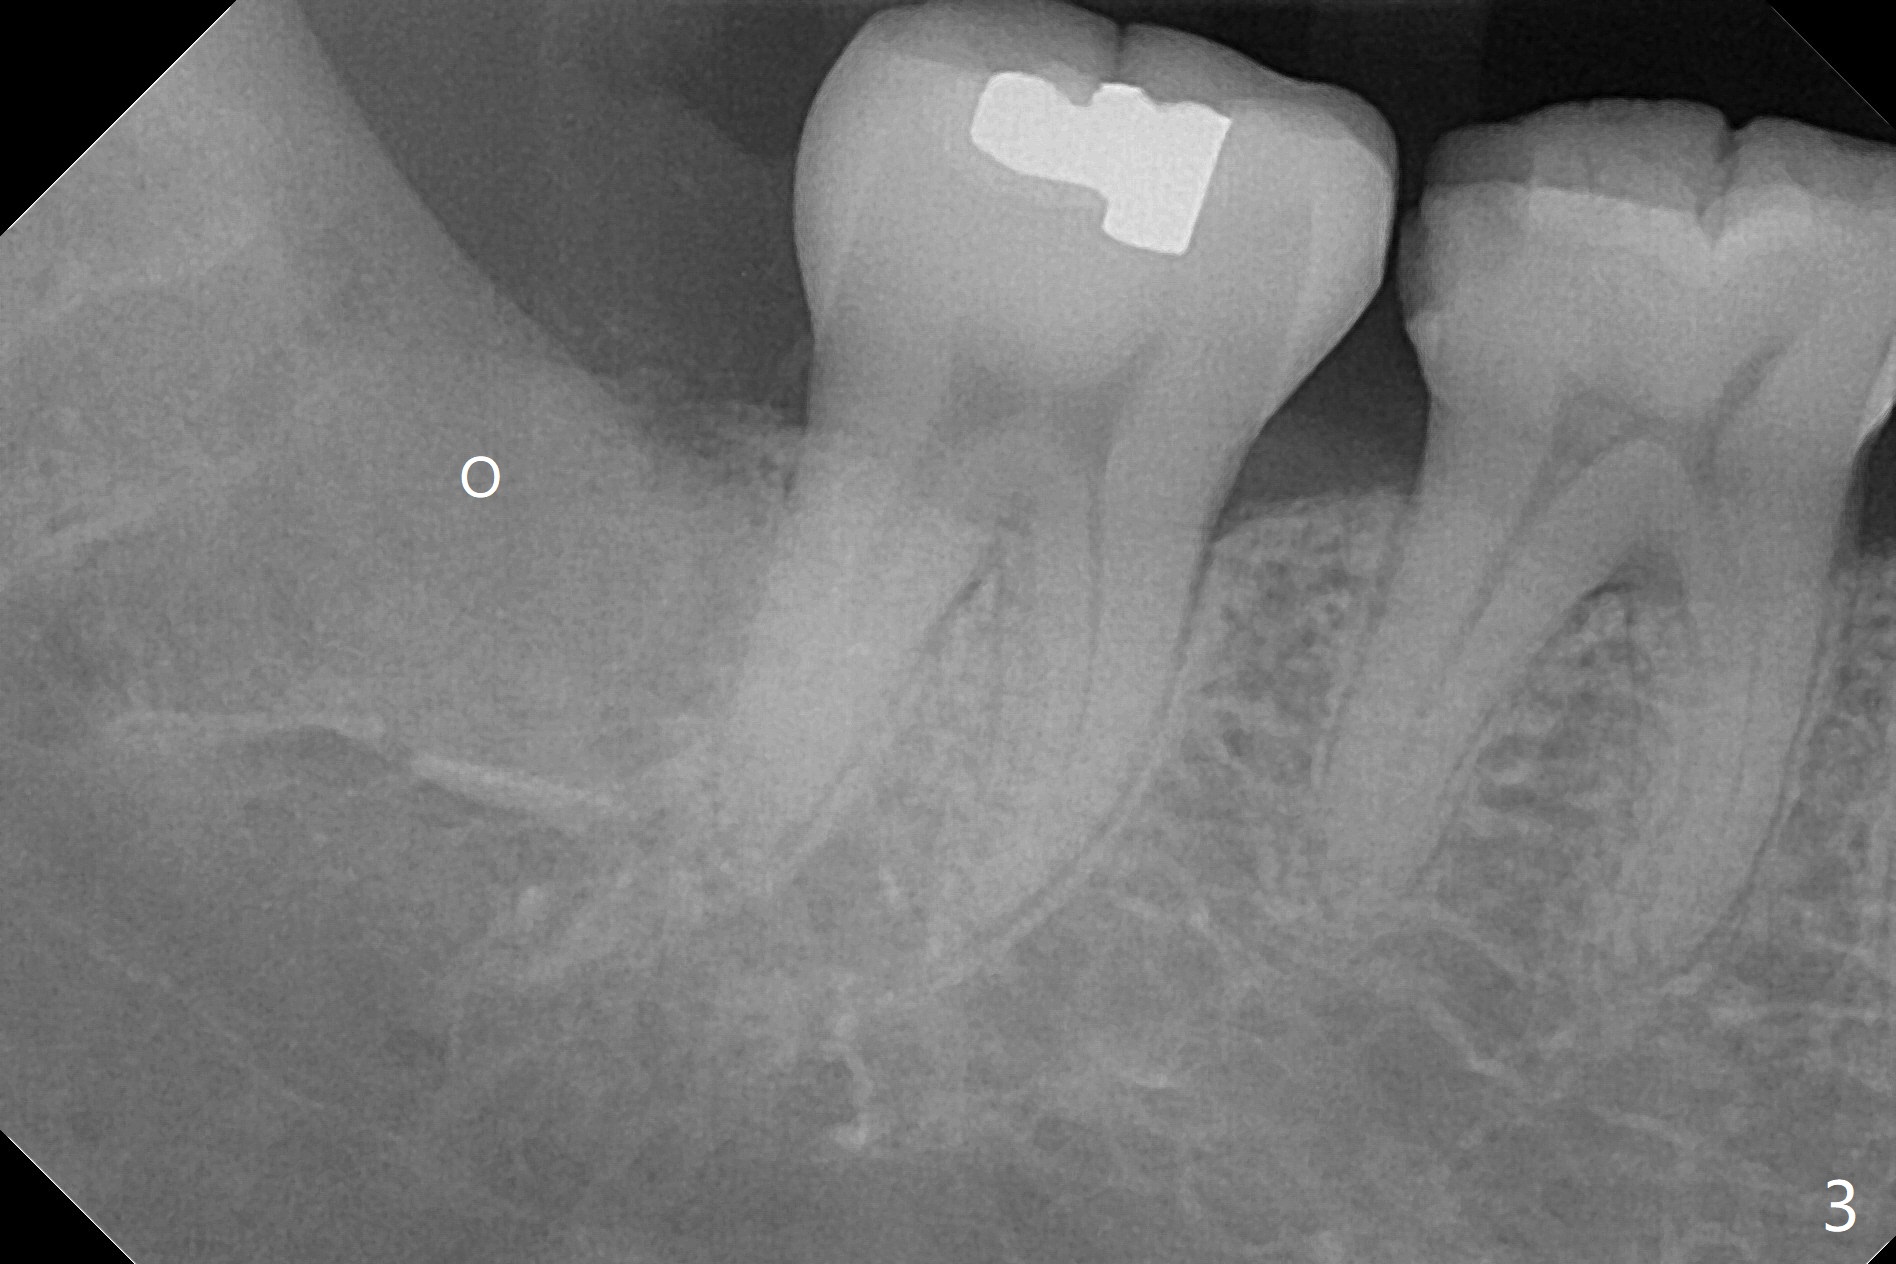

A 51-year-old woman presents to clinic because of infection in the lower right third molar (Fig.1). Although the tooth seems to be fully bony impaction, there is a sinus track with light purulent discharge after oral Amoxicillin for 5 days. In fact there is subgingival caries (Fig.2 *). The accessory incision is made mesiobuccal of #31 due to horizontal impaction. In fact the tooth is buccal and slightly mesial to #31. The impacted tooth requires several sections to be removed. Osteogen Plug is placed because of the thin bone between #31 and 32 (Fig.3 O).